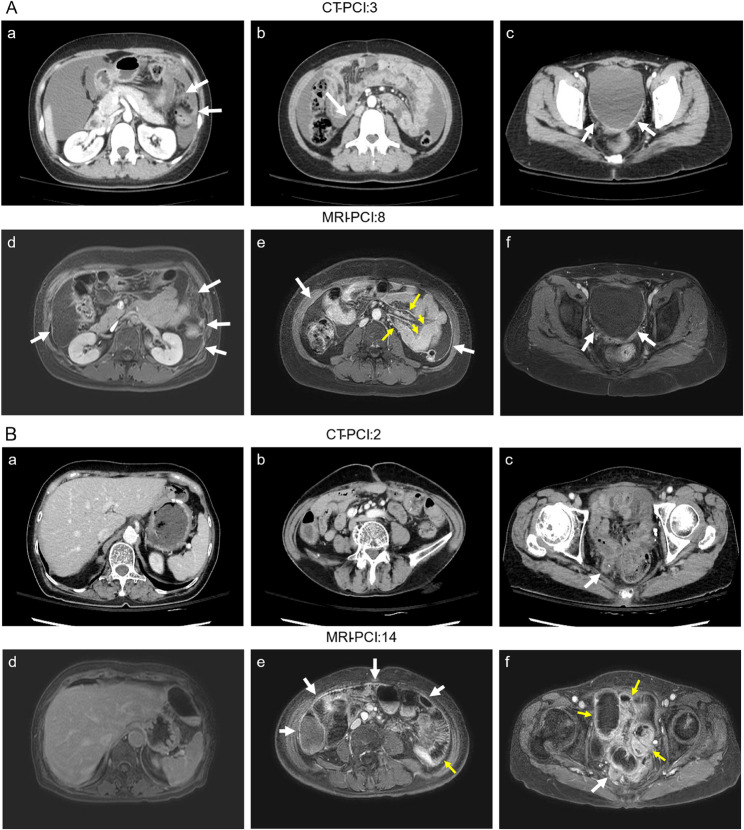

背景:细胞减少手术(CRS)联合腹腔热化疗(HIPEC)是腹膜癌患者的一种治疗选择。本研究探讨术前影响不完全CRS的因素。方法:我们回顾性回顾了2015年4月至2023年5月期间计划进行治疗目的CRS/HIPEC的188例患者。术前使用计算机断层扫描(CT) (n = 155)和/或磁共振成像(MRI) (n = 82)确定腹膜癌指数(PCI)评分。结果:完全CRS 126例(67.0%),不完全CRS 62例(32.9%)。主要原发肿瘤为结直肠癌(完全CRS: 42.9%;不完全CRS: 50.0%),其次为卵巢癌(34.1% vs. 17.7%)。多因素分析显示影像学特异性危险因素:CT模型识别腹水(OR = 4.57), 0区和11区PCI评分较高,而MRI模型识别既往化疗(OR = 101.06), 2区、3区和11区PCI评分较高。决策树分析显示,腹水患者(CT: 18.5, MRI: 6.5)与无腹水患者(CT: 8.5, MRI: 12.5)相比,腹水改变了PCI阈值。两种成像方式显示PCI总评分与手术结果一致(ICC = 0.656和0.678),0-8区比9-12区相关性更强。小肠区域准确性较差,11区敏感度最低。结论:腹水和术前影像学确定的特定区域PCI评分较高与不完全CRS风险增加相关。这些发现可以改善腹膜癌CRS/HIPEC患者的选择和术前计划。

Methods: We retrospectively reviewed 188 patients scheduled for curative-intent CRS/HIPEC between April 2015 and May 2023. Preoperative peritoneal cancer index (PCI) scores were determined using computed tomography (CT) (n = 155) and/or magnetic resonance imaging (MRI) (n = 82).

Results: Complete CRS was achieved in 126 patients (67.0%) and incomplete CRS in 62 (32.9%). Colorectal cancer was the predominant primary tumor (complete CRS: 42.9%; incomplete CRS: 50.0%), followed by ovarian cancer (34.1% vs. 17.7%). Multivariate analysis revealed imaging-specific risk factors: the CT model identified ascites (OR = 4.57) and higher PCI scores in regions 0 and 11, while the MRI model identified prior chemotherapy (OR = 101.06) and higher PCI scores in regions 2, 3, and 11. Decision tree analysis showed ascites altered PCI thresholds for patients with ascites (CT: 18.5, MRI: 6.5) versus without (CT: 8.5, MRI: 12.5). Both imaging modalities demonstrated moderate agreement with surgical findings for total PCI scores (ICC = 0.656 and 0.678), with stronger correlations in regions 0-8 than regions 9-12. Small bowel regions showed poor accuracy, with lowest sensitivity in region 11.